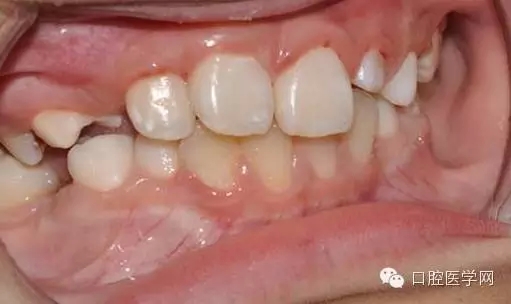

一周后拆線 :

33.webp.jpg

34.webp.jpg

術(shù)前已經(jīng)給小孩取了牙模,所以就開始

“活動(dòng)可調(diào)、釣魚式牽引器”的制作。(后續(xù)的博客會(huì)詳細(xì)的給大家講一下制作要領(lǐng),和各種卡環(huán)變異的彎制。簡(jiǎn)簡(jiǎn)單單的彎制卡環(huán)可以完勝各種焊接或鑄造。 )